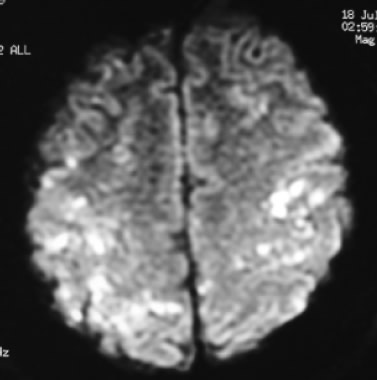

Masculino de 36 años, previamente sano, ocupación policía. Ingresó posterior a herida por proyectil de arma de fuego en pierna izquierda que condicionó fractura de peroné (Figura 1). Presentó crisis convulsivas tónico-clónicas generalizadas, estado confusional, dificultad respiratoria e hipoxemia, por lo que se ingresó a la UTI. A la exploración física con FC de 130/m, FR de 35/m, PA de 100/60, SatO2 al aire ambiente al 70%, Temperatura de 38 ºC. Con estertores crepitantes e hipoaereación bibasal de predominio izquierdo. Presencia de petequias a nivel conjuntival (Figura 2). En la citometría hemática con trombocitopenia de 150,000/mm3. En la Rx de tórax con infiltrado intersticial bibasal de predominio izquierdo (Figura 3). En la angiotomografía computada de tórax se observó infiltrado intersticial y áreas de condensación de predominio basal y no se observaron coágulos en el sistema arterial pulmonar. La resonancia magnética cerebral con imágenes hiperintensas corticales bilaterales (Figura 4).

Figura 4. Resonancia magnética nuclear en donde se observan múltiples imágenes hiperintensas compatibles con infartos en ambos hemisferios cerebrales.

En relación con el diagnóstico por imagen es importante mencionar que un alto porcentaje de los pacientes con SEG presentan alteraciones en la radiografía de tórax en las primeras 72 h posteriores al traumatismo.11 Los hallazgos son inespecíficos y suelen corresponder a edema pulmonar e infiltrado pulmonar difuso. La TAC cerebral puede mostrar signos sugerentes de embolia grasa como focos de hipodensidad o infartos hemorrágicos localizados, pero en la mayoría de las ocasiones suele ser normal. Los hallazgos de la IRM del enfermo son similares a los descritos en otros artículos, consistiendo en múltiples lesiones hiperintensas en secuencias con TR largo distribuidos predominantemente en la sustancia blanca.12 El número de lesiones se correlaciona con la escala de coma de Glasgow. La restricción de la difusión evidencia el edema citotóxico que permite el diagnóstico precoz, previo a la aparición del edema vasogénico. Estas lesiones son secundarias a la ruptura de la barrera hematoencefálica, probablemente explicada por el efecto químico directo de los ácidos grasos.